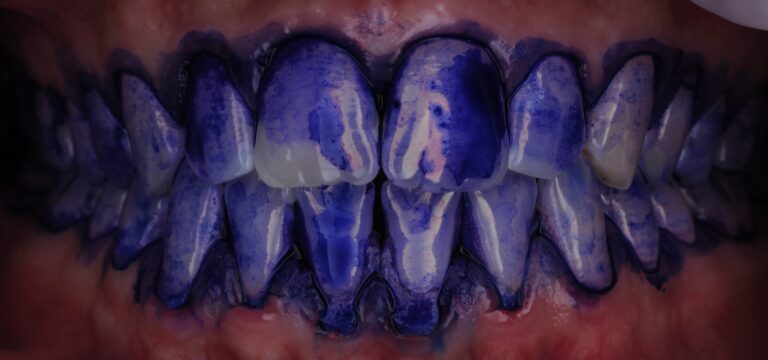

- Окрашивание налёта с помощью специального красителя:

- Визуализация налёта позволяет показать пациенту проблемные зоны.

- Цветовая индикация помогает отличить свежий налёт от старого:

- Тёмно-фиолетовый — застарелый налёт

- Светло-розовый/голубой — свежий налёт

- Это важно для мотивации и обучения: пациент наглядно видит, где недочищает.